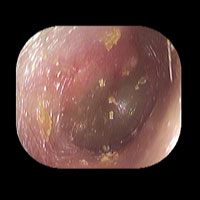

右急性中耳炎(中等症)

鼓膜がやや赤くなっています。鼓膜の奥に膿が透けて見えています。鼓膜の腫れはありません。抗生剤の内服で鼓膜切開を行わずに16日目で治りました。

初診日